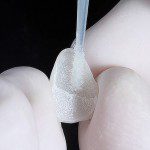

Os recursos utilizados para o desgaste proximal do esmalte são apresentados no grupo de imagens 12, desde um preparo com ponta diamantada cônica longa (12a), ou um disco diamantado, que permite um desgaste mais fino (b), ou até o uso de lixa de aço diamantada para um desgaste mais delicado (c).

- Figura 12a

- Figura 12b

- Figura 12c